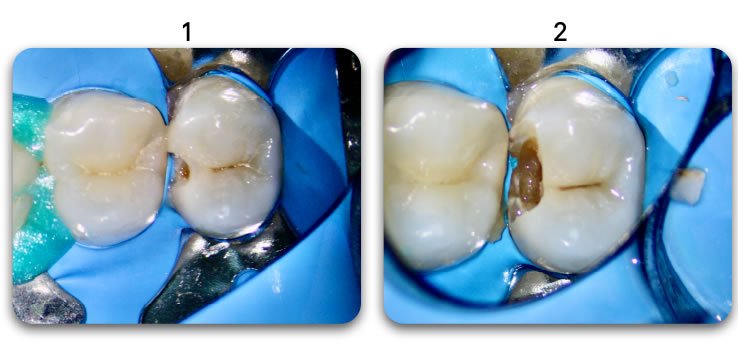

Retain 100% of remaining healthy tooth structure

- Biolight® DRILL-FREE adapts to all shaped canals, while conserving all remaining healthy tooth structure.

- There is no need to drill out portions of canals to accommodate post spaces.

- Easily place multi-posts in multiple canals as the post bends with the natural canal shape.